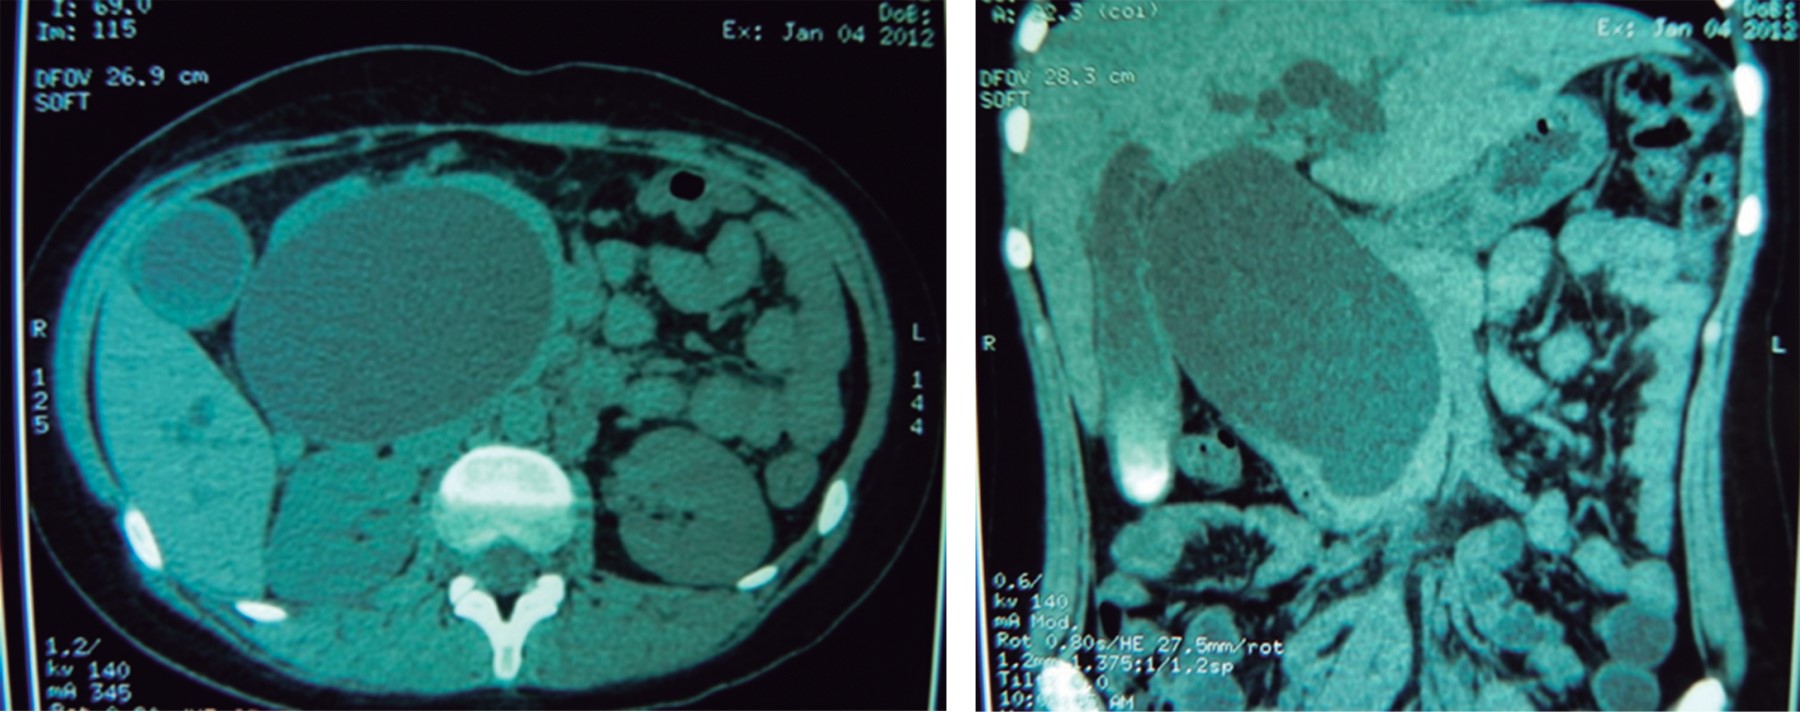

Caso clínico 1: femenino de 14 años, cuatro años de evolución con dolor tipo cólico en hipocondrio derecho. Cuatro meses previos a su ingreso presentó episodios más frecuentes, agregándose ictericia, coluria, acolia, náuseas y vómito. Ingresó con ictericia, dolor a la palpación en hipocondrio derecho y epigastrio, y una tumoración de aproximadamente 15 × 15 cm. Las pruebas de función hepática mostraron hiperbilirrubinemia mixta (bilirrubina total: 7.1 mg/dl, bilirrubina directa: 3.7 mg/dl, aumento de la fosfatasa alcalina: 651 U/l). El ultrasonido reveló colecistitis litiásica, coledocolitiasis versus quiste de colédoco; la tomografía axial computarizada: colecistitis litiásica y dilatación quística de la vía biliar (Figura 1). La colangiorresonancia mostró un quiste de colédoco de 72 mm con dilatación de la vía biliar intrahepática (Figura 2). Se realizó cirugía electiva, se encontró vesícula biliar con litos y un quiste de colédoco tipo I de la clasificación de Todani adherido a duodeno de 17 × 10 × 10 cm (Figura 3).

Figura 1